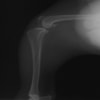

・術後レントゲン

手術前TPA 28.4° が術後TPA 11.7° に矯正されました。

術前TPA計測

術後TPA計測

手術後

手術前